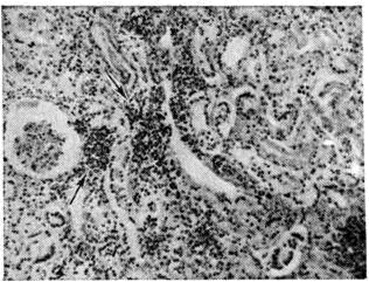

Поражения почек при Лептоспироз наиболее часто выявляют в поздние сроки болезни. В это время лептоспиры начинают выводиться с мочой. На вскрытии почки значительно увеличены в размерах, дряблые, на разрезе желтушные. Могут встретиться кровоизлияния в мозговое вещество и околопочечную клетчатку. Гистологически преобладает картина нефроза, вплоть до некроза эпителия извитых канальцев. Клубочки поражаются меньше, чем канальцы. В просвете канальцев могут быть обнаружены лептоспиры. Наряду с явлениями нефроза возможны мелкоочаговые круглоклеточные инфильтраты в интерстиции почки (рисунок 3).

Рис. 3. | ||